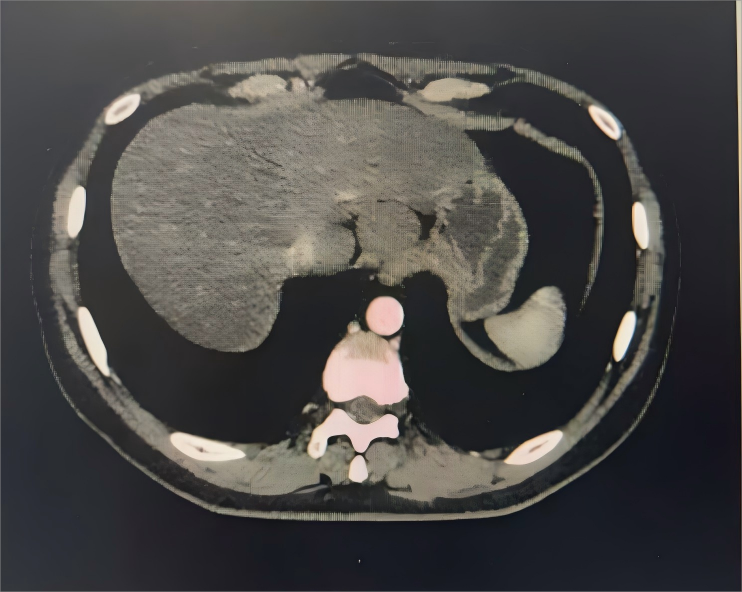

半月余前,患者吴先生于外院体检时发现食管下段肿物,虽无吞咽困难等症状,为求进一步诊治,经人介绍来到西安市第三医院。经消化内镜中心胃镜检查,考虑为食管良性肿瘤,随后转入胸外科接受治疗。

据该院胸外科主任杨锋介绍,食管良性肿瘤在食管肿瘤中仅占约1%,发病年龄较轻,症状进展缓慢。对于肿瘤较小、无明显临床症状的患者可暂时观察,但若肿瘤来源于肌层,则建议手术治疗。手术需精准把握解剖层次,避免损伤黏膜,降低术后并发症风险。

经全面评估并与消化内科专家共同讨论,一致认为患者手术指征明确,决定行腔镜辅助食管肿物切除术。术中,在麻醉科团队的全程护航下,消化内科专家通过胃镜精准定位肿瘤位置,胸外科手术团队精细操作,完整切除肿物并确认黏膜完好无损。